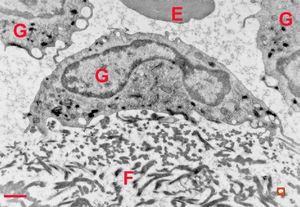

M,7m. | a formation of Birbeck granule(Langerhans granule, X-granule) - skin, histiocytosis X

M,7m. | Birbeck granules (Langerhans granules, X-granules) - skin, histiocytosis X

M,7m. | Birbeck granules (Langerhans granules, X-granules) - skin, histiocytosis X

M,1y. | Birbeck granules (X-granules) - skin, histiocytosis X

M,1y. | Birbeck granule (X-granule) - skin, histiocytosis X